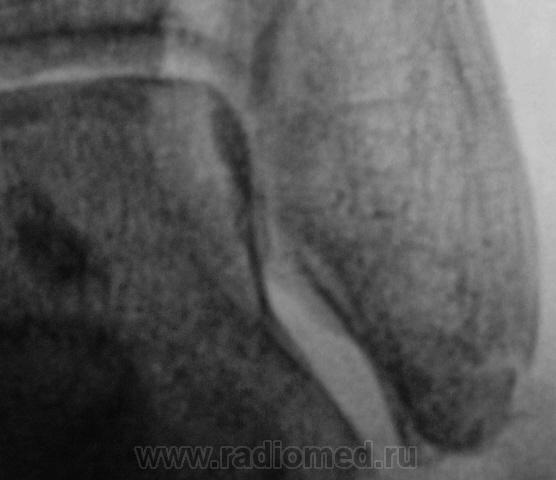

Трах... и вырос "грибок" на таранной...

Грибок этот не "трахогенной" природы. У меня вообще сомнения, что это вырост кости.

Лодыжка срастется, никуда не денется. А вот оссифицирующий апоневрозит и данный то-ли экзостоз, то-ли оссификат капсулы будут периодически доставать и пациента, и врача-куратора.

Больше склоняюсь к хондромному телу, хоть в данном месте не встречал

Грибок этот не "трахогенной" природы. У меня вообще сомнения, что это вырост кости.  +1 !     Больше похоже на обызвествление сосудов . А хондроматоз - не подходит по локализации , хотя сама тень похожа внешне .